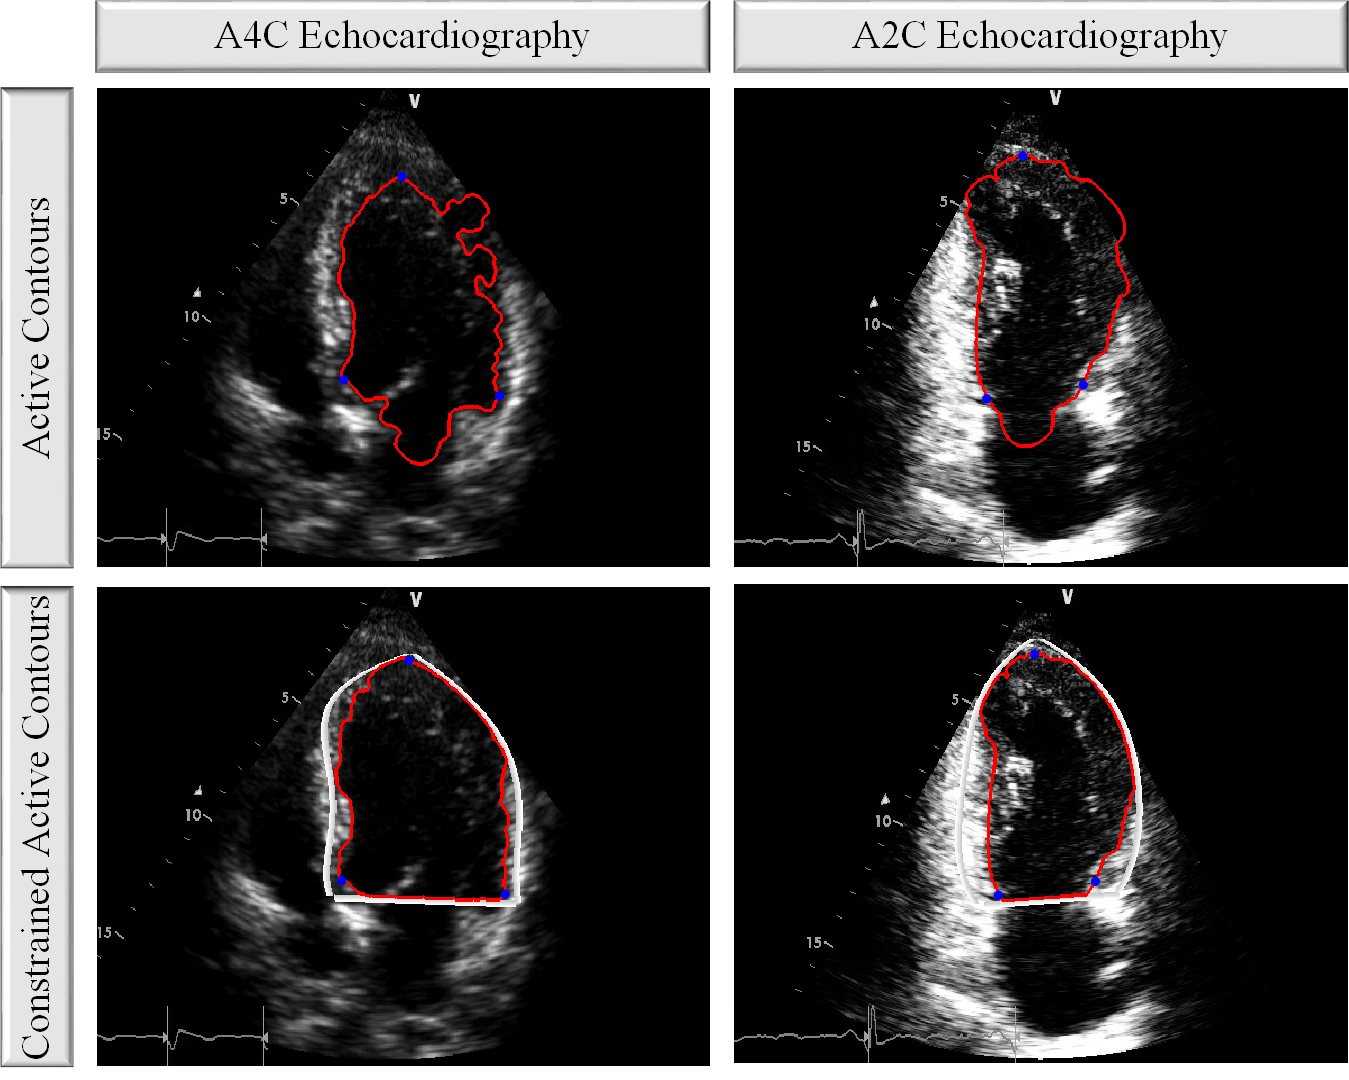

Refer to caption

Figure 3: The comparison of the original and constrained active contours. In both A4C and A2C views, the constrained active contours can extract the endocardial boundary more accurately.

In the first stage of the APs formation, the Ridge Polynomials (RPs) are formed on the LV wall. In echocardiography, the LV wall may partially be missing or invisible due to low quality. Thus, in the evolvement process of the active contours, the contour may escape from the chamber causing inaccurate segmentation of the endocardial boundary. Therefore, the RPs are first created to constrain the active contours as illustrated in Fig. 3. In the second stage of the proposed method, we initialize an active contour from inside the chamber. The initial mask for the contour is located in the middle of the LV as a mini-version of the current frame’s RPs. The aim is to evolve an active contour to detect and extract the endocardial boundary of the LV wall. A typical edge detector is expressed as follows:

where g𝑔g is a function with positive and decreasing values, z𝑧z is an image, and the edges of z𝑧z are detected at the locations where the gradient is zero. However, detecting the edges of images with rough and discontinuous objects is challenging with the gradient method since generally gradient is not zero on that particular edges. Thus, Chan-Vese [38] active contour method is utilized since its stopping criteria do not depend on the gradient. Therefore, it is suitable especially for echocardiography, where there are discontinuities (even though it has been minimized by RPs) and rough edges on the LV wall due to the high level of noise and acquisition. Once the active contour has converged to the endocardial boundary, the APs can then be formed over the evolved active contour. As shown in Fig. 3, the active contour may be noisy with severe discontinuities on the LV wall. In order to achieve a smooth endocardial boundary segmentation, the evolved active contour is divided into two sections. The left part of the contour corresponds to the active contour points from start to apex, whereas the right part is from apex to end. After the division, we compose 4thlimit-fromsuperscript4th4^{\text{th}}-order smooth polynomials each of which is fitted to the equally distanced 999 points from both right and left parts to form APs that are the final form of the endocardial boundary. Thus, APs provide a robust and smooth endocardial boundary for MI diagnosis.